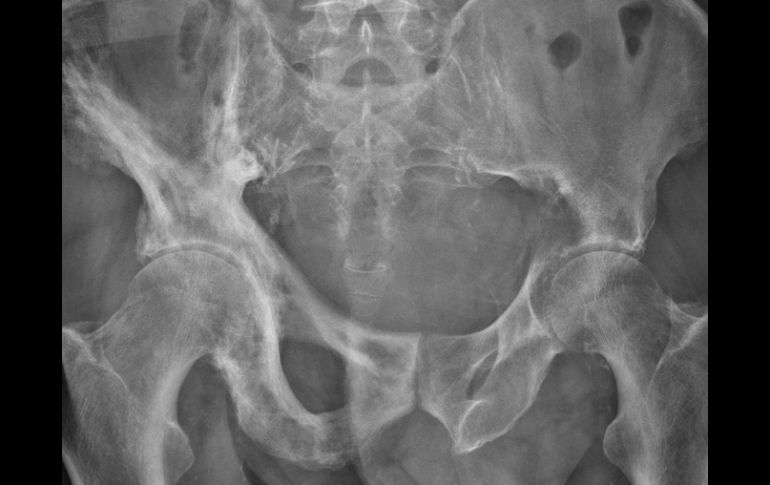

Tecnología | El padecimiento se manifiesta en algunos casos por una enfermedad hereditaria Osteoporosis, aun más riesgosa si existe diabetes La osteoporosis se manifiesta por una mala alimentación, la falta de ejercicio y en algunos casos es una enfermedad hereditaria Por: EL INFORMADOR 8 de mayo de 2011 - 20:04 hs La diabetes aumenta el riesgo a tener mayores complicaciones ante la constante pérdida de calcio. Agencia ID / CIUDAD DE MÉXICO (08/MAY/2011).- De ser una enfermedad silenciosa, la osteoporosis se ha convertido ya en un problema de salud pública que afecta a casi 20 por ciento de las mujeres tras presentar menopausia y pone, además, a quienes padecen diabetes en mayor riesgo de sufrir fracturas de hueso debido a una mala alimentación y pérdida de minerales. La osteoporosis es un padecimiento crónico-degenerativo que aqueja en mayor medida a las mujeres, mediante una ruptura ósea por la disminución de minerales como calcio y el fósforo, lo que aumenta la posibilidad de conducir a fisuras en diferentes zonas del cuerpo. Al respecto, la jefa de servicio de endocrinología del Hospital General de México, doctora Sara Arellano Montaño, comentó que la osteoporosis se manifiesta por una mala alimentación, la falta de ejercicio y en algunos casos es una enfermedad hereditaria. Sin embargo, la menopausia es el factor que más influye en el desarrollo del padecimiento en las mujeres, sobre todo aquellas mayores de 40 años, ya que la escasez de estrógenos (hormonas) en la función ovárica provoca una disminución total o parcial de la asimilación de minerales por parte del sistema óseo, puntualizó la especialista en anatomía. Cuando estos problemas alcanzan a una persona que vive con diabetes mellitus, explicó Arellano Montaño, suele presentar una ruptura en el metabolismo intermedio; es decir, interrumpe el medio que requiere consumir energía, vitaminas y minerales para mantener en buen funcionamiento el proceso metabólico. Es claro que la diabetes aumenta el riesgo a tener mayores complicaciones ante la constante pérdida de calcio; sin embargo, el quebrantamiento de huesos no sólo es propio de la osteoporosis, sino también corresponde a problemas de riñón que pueden detonar diversas fracturas óseas. Al mostrar insuficiencia renal, el individuo tiende a desarrollar un trastorno conocido como microalbuminuria, signo provocado por el mal funcionamiento del riñón debido a niveles altos de glucosa en la sangre (hiperglucemia), la cual llevaría a la pérdida de proteínas sanguíneas y nutrientes para derivar en osteoporosis, detalló la doctora Arellano Montaño. La endocrinóloga expuso: “Para tales casos la complicación también puede incidir en mujeres jóvenes, quienes aún no llegan a la menopausia e incluso están en una etapa reproductiva sin afecciones hormonales, pero que la causa de aumento de riesgo fue la insuficiencia renal”. Sin previo aviso a quién afecta En México, cifras de la Asociación Mexicana de Metabolismo Óseo y Mineral (AMMOM) reportan que al menos 17 por ciento de las mujeres y alrededor de 9 por ciento de los hombres, de 50 años y más, sufren osteoporosis en la columna lumbar, mientras que en ese orden 16 y 6 por ciento la padecen en la cadera. Ante esas fracturas, que también sufren los pacientes con diabetes, indicó la titular del servicio de Endocrinología, otra de las zonas del cuerpo que también llegan a fisurarse son las manos. “Pero, a pesar de ello, esta enfermedad crónico-degenerativa no se asocia con el desequilibrio de los niveles de glucosa en la sangre”, subrayó. Si bien la osteoporosis no causa inconvenientes glicémicos, en una persona que requiere un proceso quirúrgico debido a rupturas óseas y muestra inestabilidad de glucosa por otras razones, primero se tienen que controlar los niveles de azúcar para realizar la cirugía, comentó Arellano Montaño. Pero la experta reconoció que la fase de recuperación suele ser más tardada y requiere de cuidados mayores, ya que quien vive con diabetes es propenso a adquirir alguna infección y requiere mayor tiempo de cicatrización, en comparación con aquel que sólo tiene osteoporosis. Sorprende a la osteoporosis Es de destacar que para ambas enfermedades crónico-degenerativas, prevenir es el principio para evitar daños más severos. En el caso de la osteoporosis, impedir un déficit de hormonas y con ello alguna fractura ósea, y en diabetes, diversas afecciones como pérdida de la vista, insuficiencia renal e infartos, entre otros. Para los pacientes que manifiesten estas enfermedades es recomendable modificar su estilo de vida a fin de adquirir nuevos hábitos alimenticios, realizar alguna actividad física y un monitoreo de glucosa constate, además de un tratamiento farmacológico prescrito por el médico para reducir la pérdida de minerales y evitar otros trastornos, concluyó la doctora Sara Arellano Montaño. Cabe mencionar que la proporción mineral de la masa ósea se establece mediante una densitometría ósea, cuya prueba establece que la presencia de osteoporosis es por una pérdida de más de 2.5 desviaciones estándar, orden que refiere a la fragilidad de fractura. Con información de Agencia ID Temas Ciencia médica Enfermedades Diabetes Osteoporosis Lee También Nobel de Química premia el desarrollo de estructuras metal-orgánicas Nobel de Física para Clarke, Devoret y Martinis por descubrimiento sobre fenómenos cuánticos Esclerosis: Qué es y cuáles son los daños que deja la enfermedad Nobel de Medicina premia investigación sobre el control del sistema inmunitario Recibe las últimas noticias en tu e-mail Todo lo que necesitas saber para comenzar tu día Registrarse implica aceptar los Términos y Condiciones